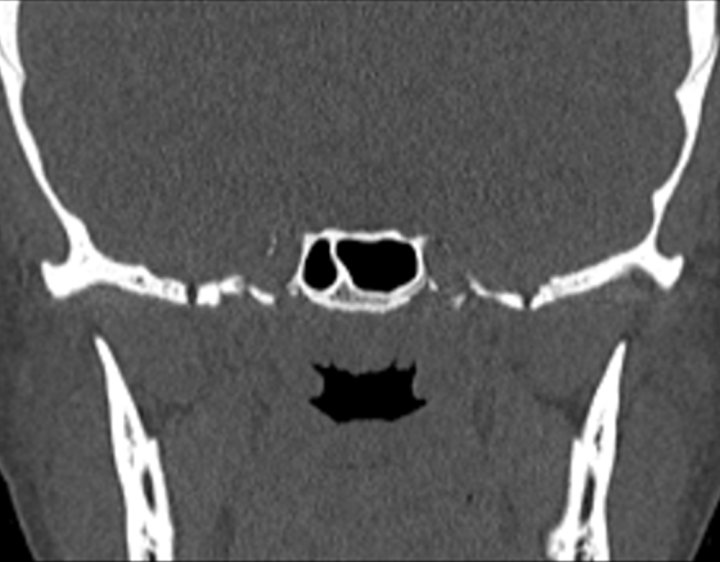

001